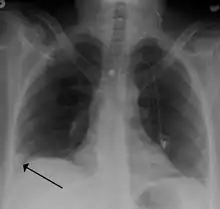

| A lung illustration depicting a pulmonary embolism as a thrombus (blood clot) that has travelled from another region of the body, causes occlusion of the pulmonary bronchial artery, leading to arterial thrombosis of the superior and inferior lobes in the left lung | |